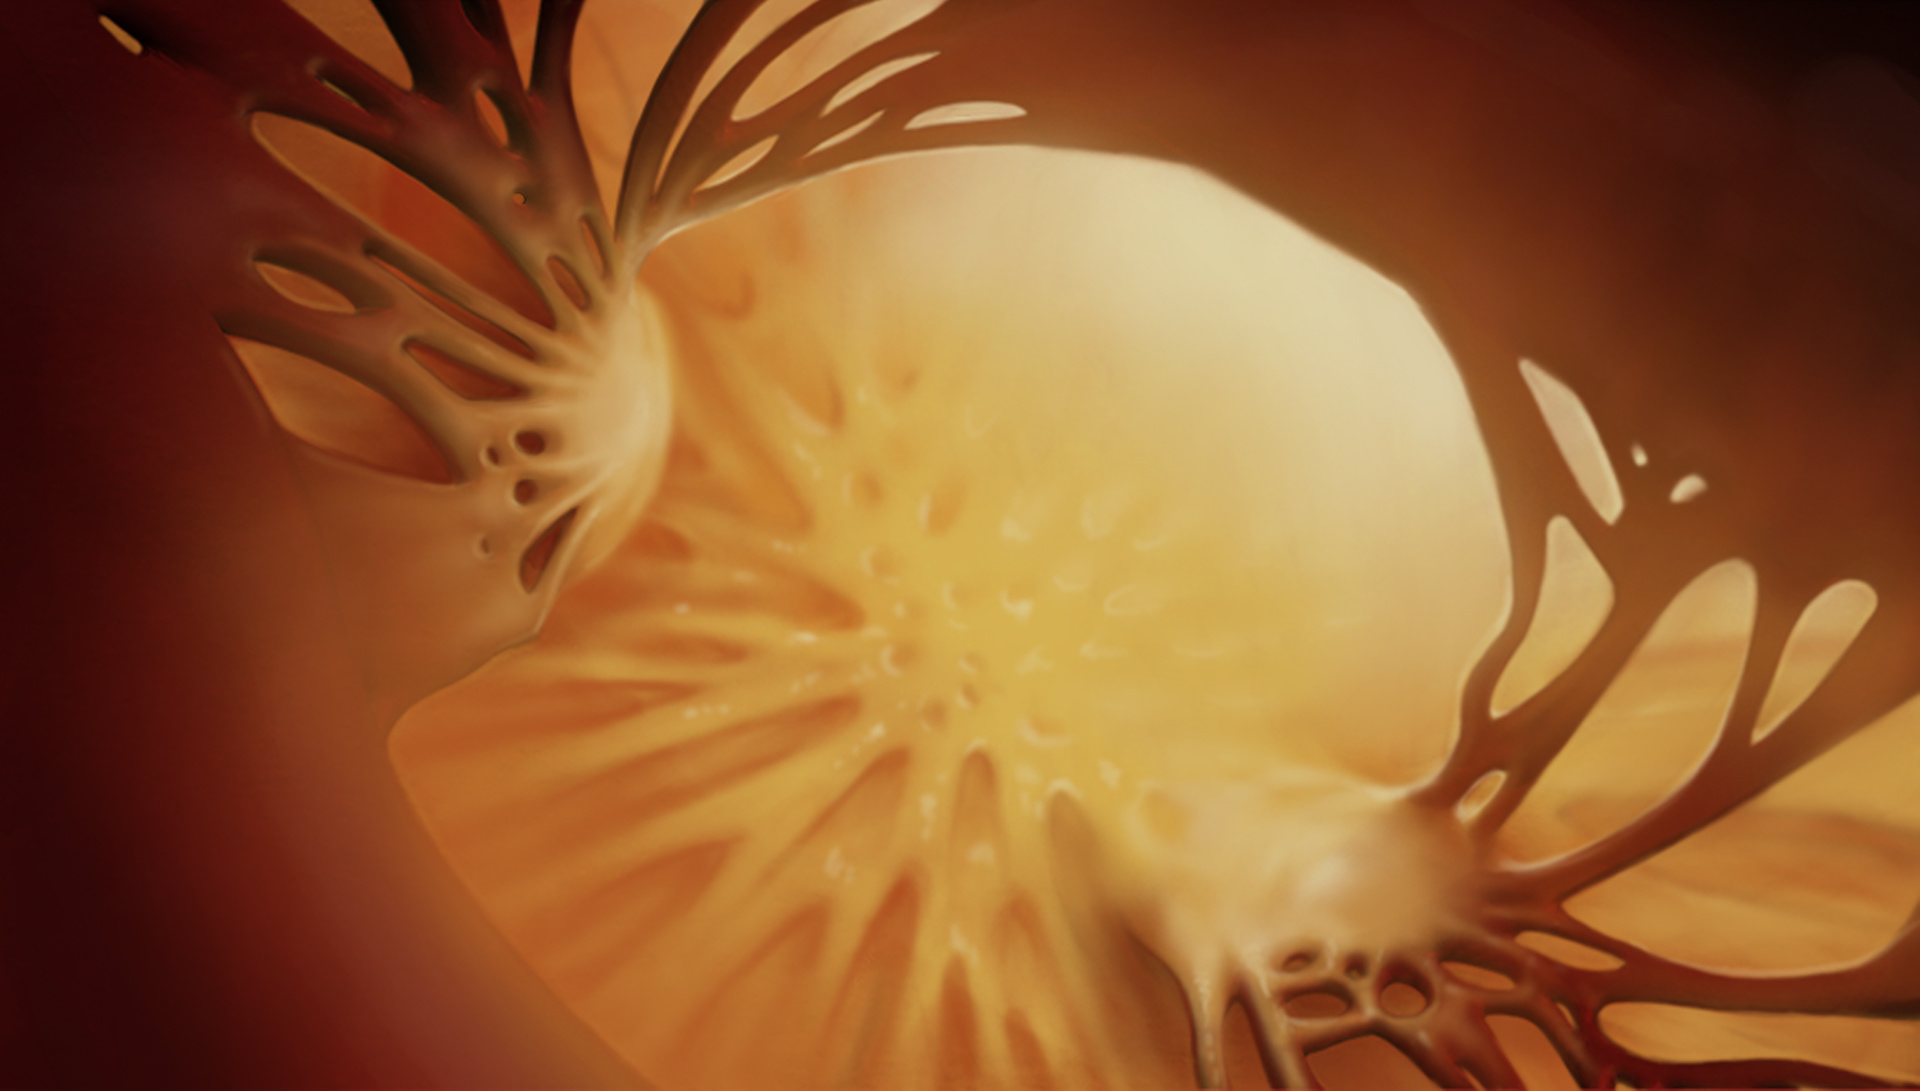

I created a story board of what it would look like to fly through this heart

This shows the progression of what Aortic Valve Stenosis looks like.